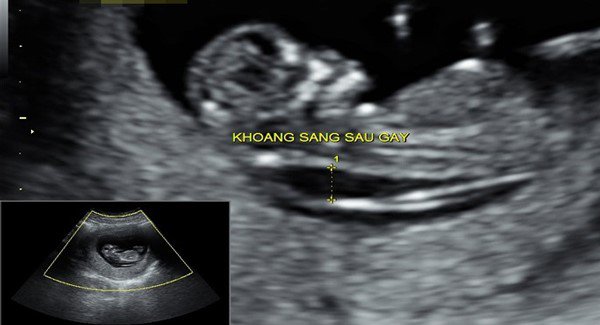

Khi kết hợp sự thay đổi của các chỉ số này với độ mờ da gáy (NT), chiều dài đầu mông (CRL) của thai nhi và một số thông số khác bằng phần mềm chuyên dụng để giúp bác sĩ đánh giá nguy cơ dị tật.

9.2 Độ mờ da gáy bình thường có cần làm Double test

Độ mờ da gáy thường được kết hợp với Double test để xác định dị tật Down, việc này giúp tăng khả năng xác định nguy cơ dị tật thai nhi. Bên cạnh đó, Double test còn giúp sàng lọc thêm 2 loại nguy cơ khác là Edwards (Trisomy 18) và Patau (Trisomy 13). Vì thế, dù kết quả siêu âm đo độ mờ da gáy bình thường thì vẫn nên thực hiện Double test.

Độ mờ da gáy bình thường vẫn nên làm xét nghiệm sàng lọc trước sinh double test